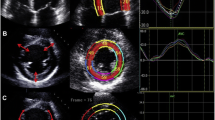

The effects of LDR could contribute to antioxidative potential, reduce cancer incidence, and modulate a variety of immune responses [130]. Several experimental findings were reviewed recently and showed that LDR induces anti-inflammatory properties and may thereby protect against inflammatory disease [131]. We have additionally demonstrated that diabetic mice exposed to repetitive LDR at 25 mGy showed significant prevention of diabetes-induced renal and cardiac damage in type 1 and type 2 diabetes in animal studies. Exposure of normal or tumor-bearing mice to 25–75 mGy LDR significantly prevented the tumor growth and metastasis [132]. The fact that LDR has the potential to prevent chemotherapy-induced cardiotoxicity has garnered significant interest. Based on the evidence that LDR increases antioxidant activity and DNA repairing capacity, many studies were conducted to explore the role of cardioprotective and the possible underlying mechanisms of LDR in chemotherapy with Dox. Our study [133••] demonstrated that LDR-stimulated cardiac antioxidative capacity in reducing oxidative stress derived from mitochondria-dependent ROS/RNS generation which suggests that LDR could induce adaptation of the heart to DOX-induced toxicity. In addition, the cardiac protection by LDR may attribute to attenuate DOX-induced cell death via suppressing mitochondrial-dependent oxidative stress and apoptosis signaling.